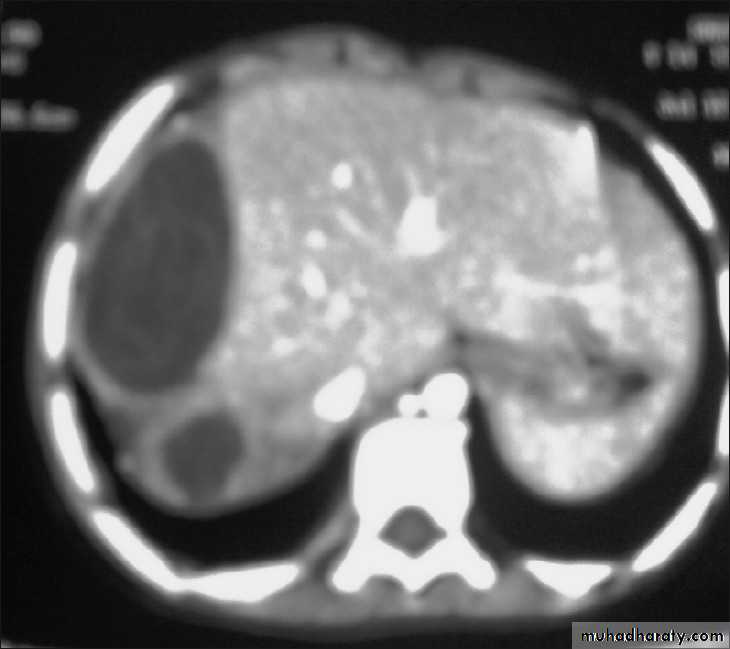

Multilocular or Alveolar Hydatid Cyst

It is the larval stage of E. multilocularis, it is composed of numerous small spaces or cavities, separated from each other by connective tissue.occasionally it may contain protoscolices.

The germinal and laminated layers are poorly developed, it has no fibrous capsule.

It is occurs usually in the liver and rarely in lung. Because of its fast growth, it is usually fatal.

• MRI & CT scan.